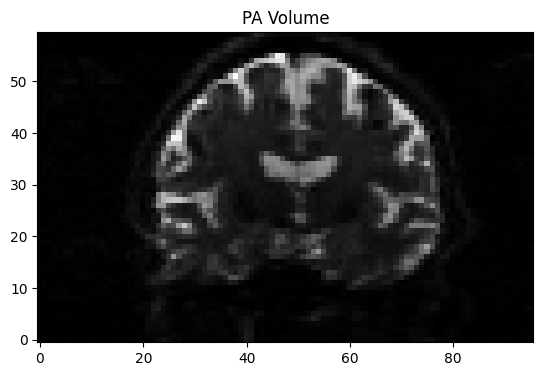

from IPython.display import display, clear_output

img = nib.load("AP_PA.nii.gz")

data = img.get_fdata()

mid_slice = data.shape[1] // 2 # middle sagittal slice

for i in range(10): # flip 10 times between AP and PA volume

for vol in range(2):

plt.imshow(data[:, mid_slice, :, vol].T, cmap='gray', origin='lower')

plt.title(f"{'AP' if vol == 0 else 'PA'} Volume")

display(plt.gcf())

time.sleep(1.0) #flip every second

clear_output(wait=True)